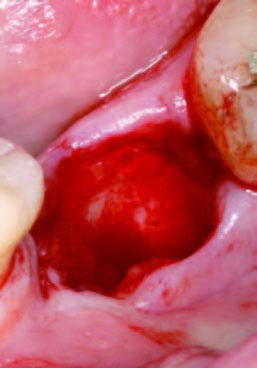

PRGFなし

抜歯直後

PRGFあり

抜歯とEndore填入

抜歯後にできた穴にPRGFを注入すると、上皮や骨の再生が促進され、短期間で穴が塞がります。また、抜歯後の痛みや腫れも軽減されるため、回復がスムーズに進みます。

一方、自然治癒の場合、穴が完全に塞がるまでに数ヶ月かかることがあります。その間に、ドライソケット(抜歯窩治癒不全)を引き起こしたり、食べ物が詰まることで痛みや悪臭が発生することもあります。